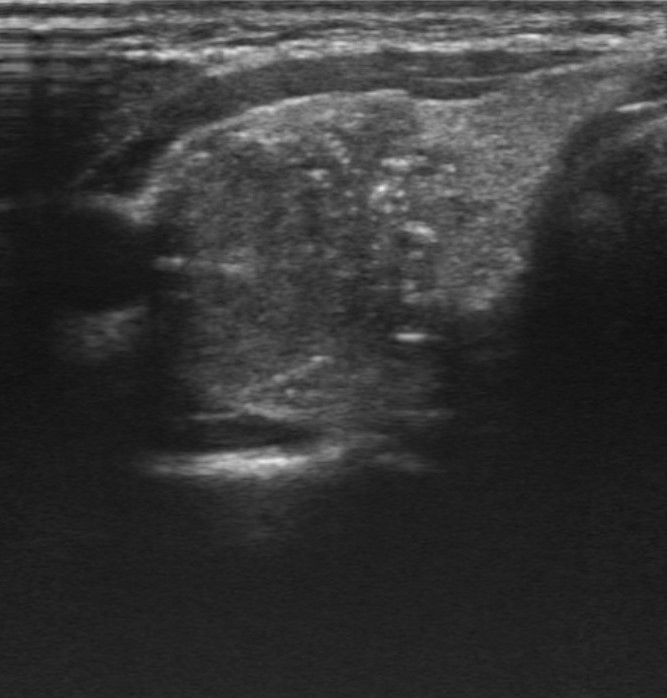

Hallazgos ecográficos

Nódulo de 16,9×15,1 mm, sólido, hipoecoico, de bordes mal definidos, más alto que ancho y con microfocos ecogénicos y calcificación periférica en anillo. Se clasifica como TIRADS 5, altamente sospechoso de malignidad e indicativo de PAAF al superar los 10 mm.

Ecografía reglada el 06/10/2025 confirma nódulo hipoecoico bien delimitado con septos refringentes. Se realiza PAAF el 09/10/2025. Citología del 16/10/2025: frotis hipercelular con pseudopapilas, núcleos irregulares y pseudoinclusiones, compatible con carcinoma papilar (Bethesda V).